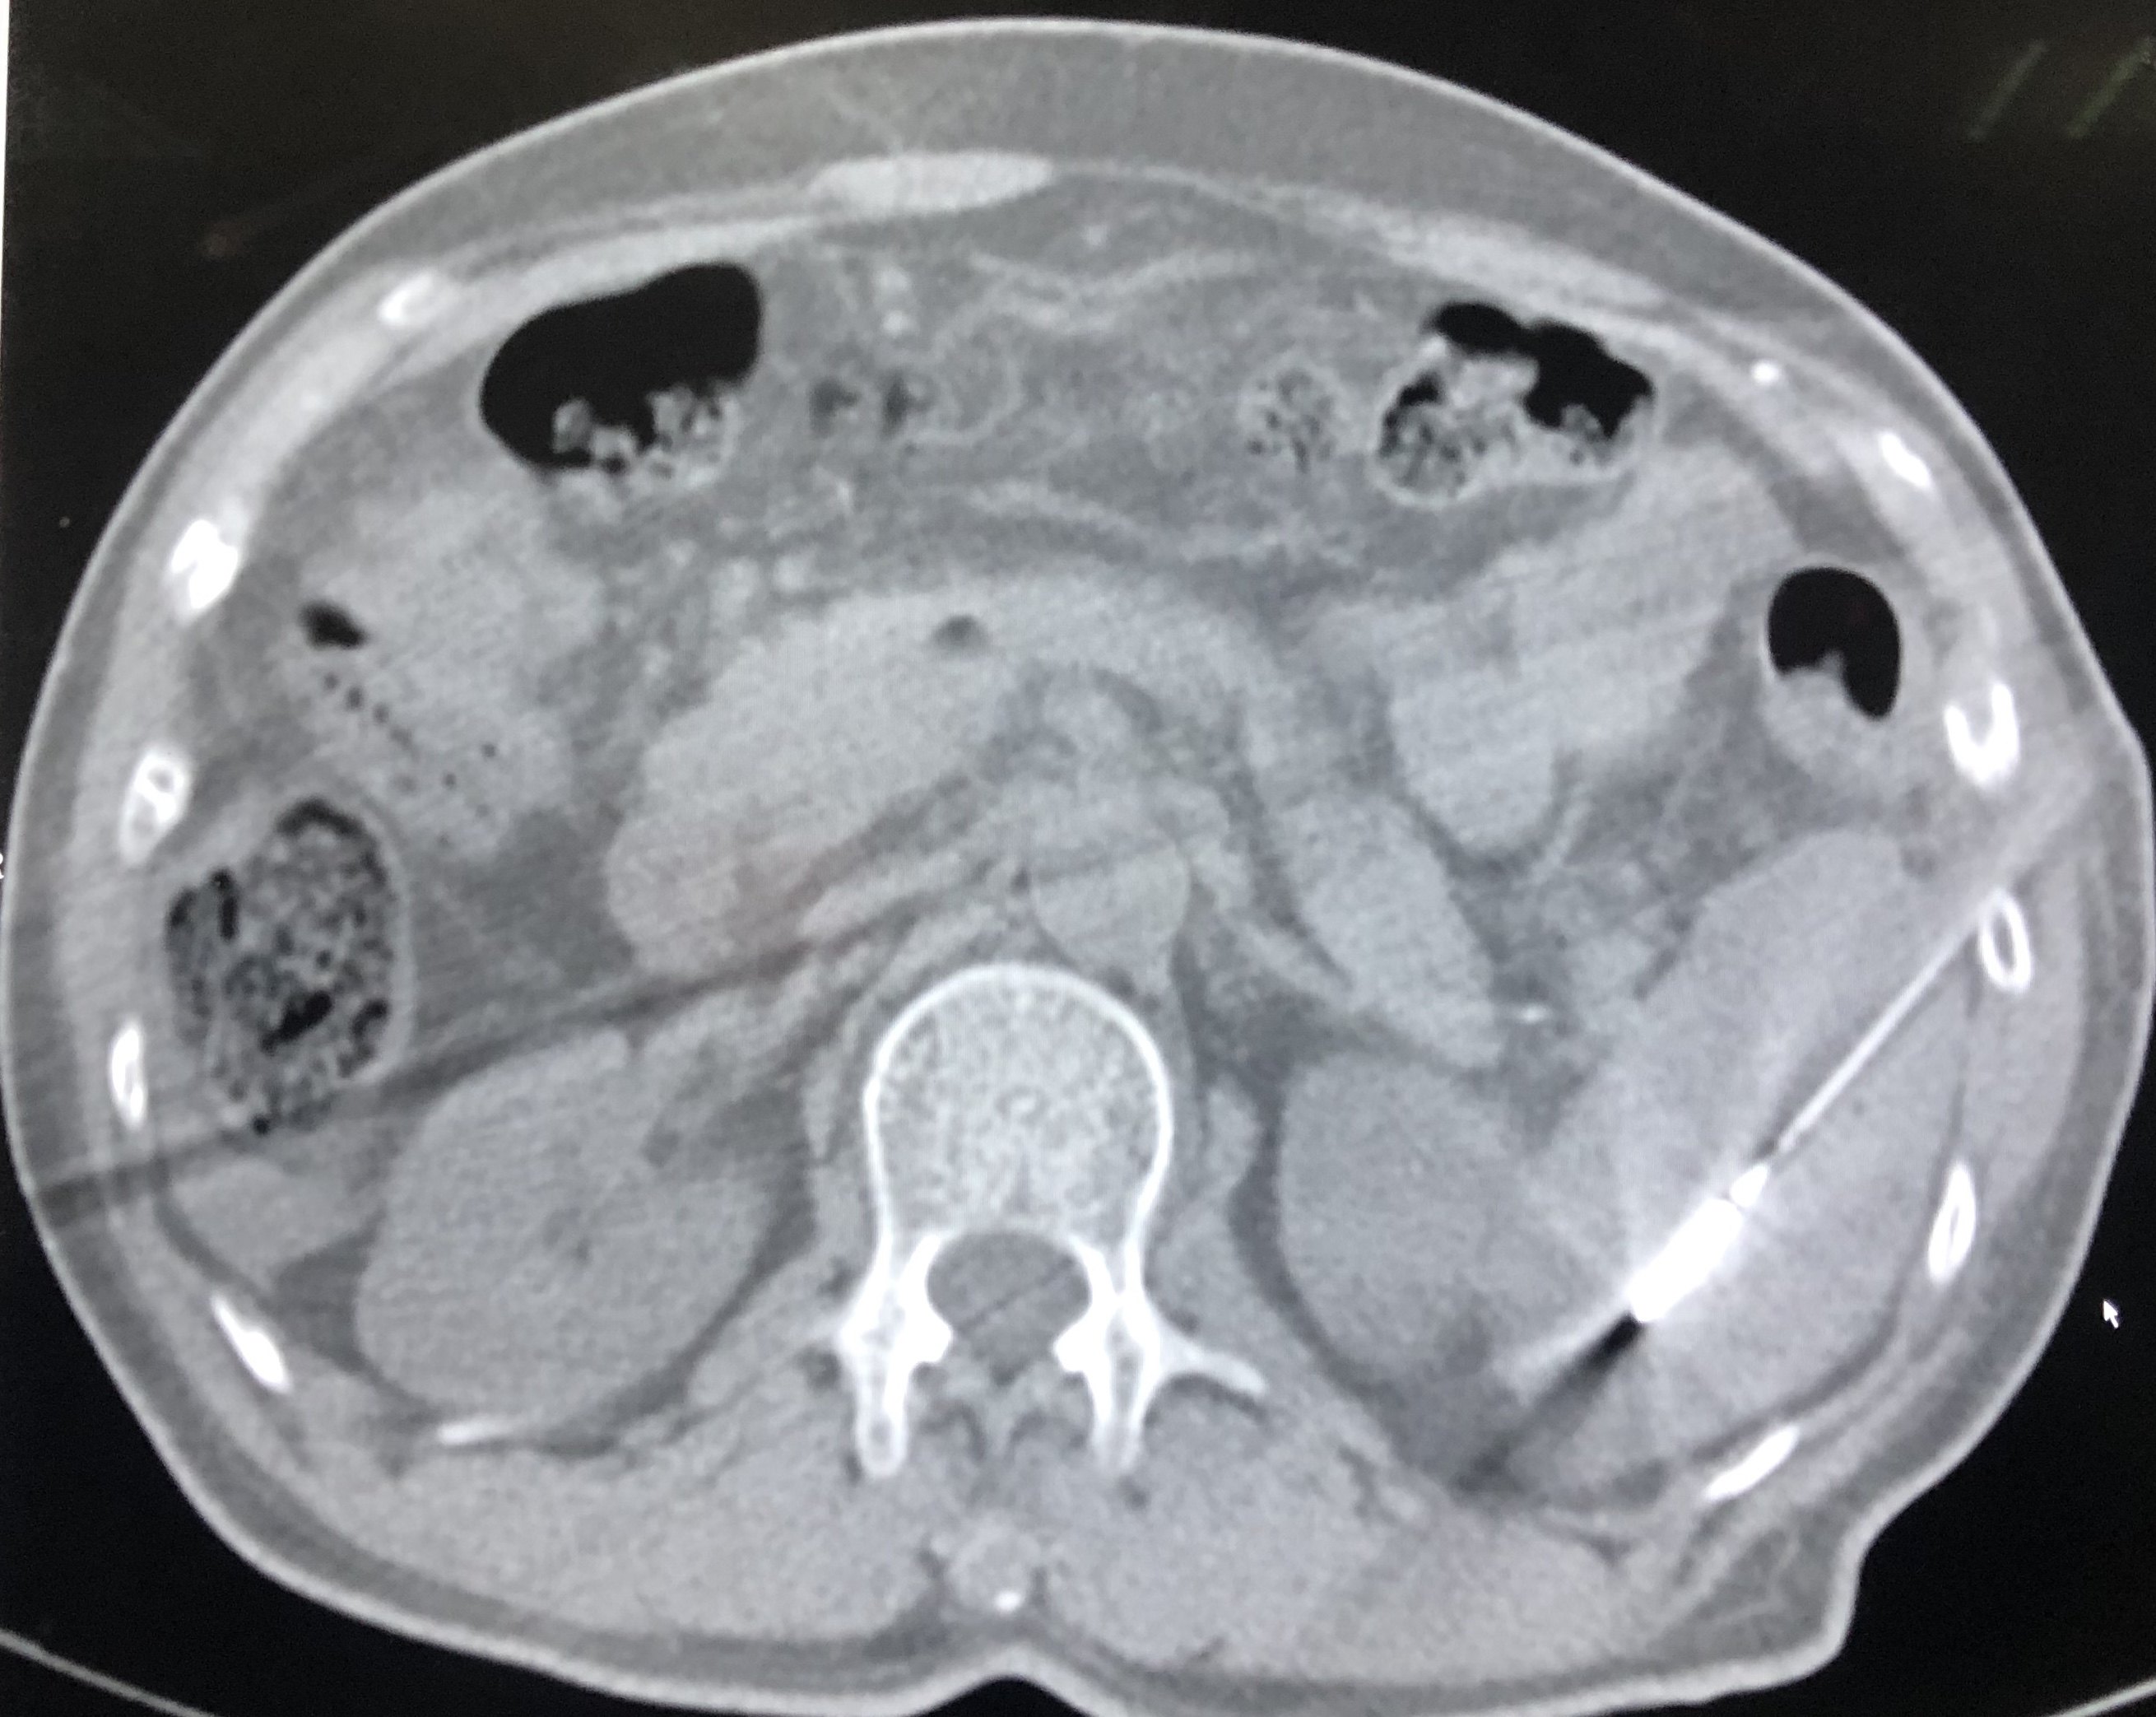

脾消融后复查脾脏见大片状低密度坏死区为消融术后改变。